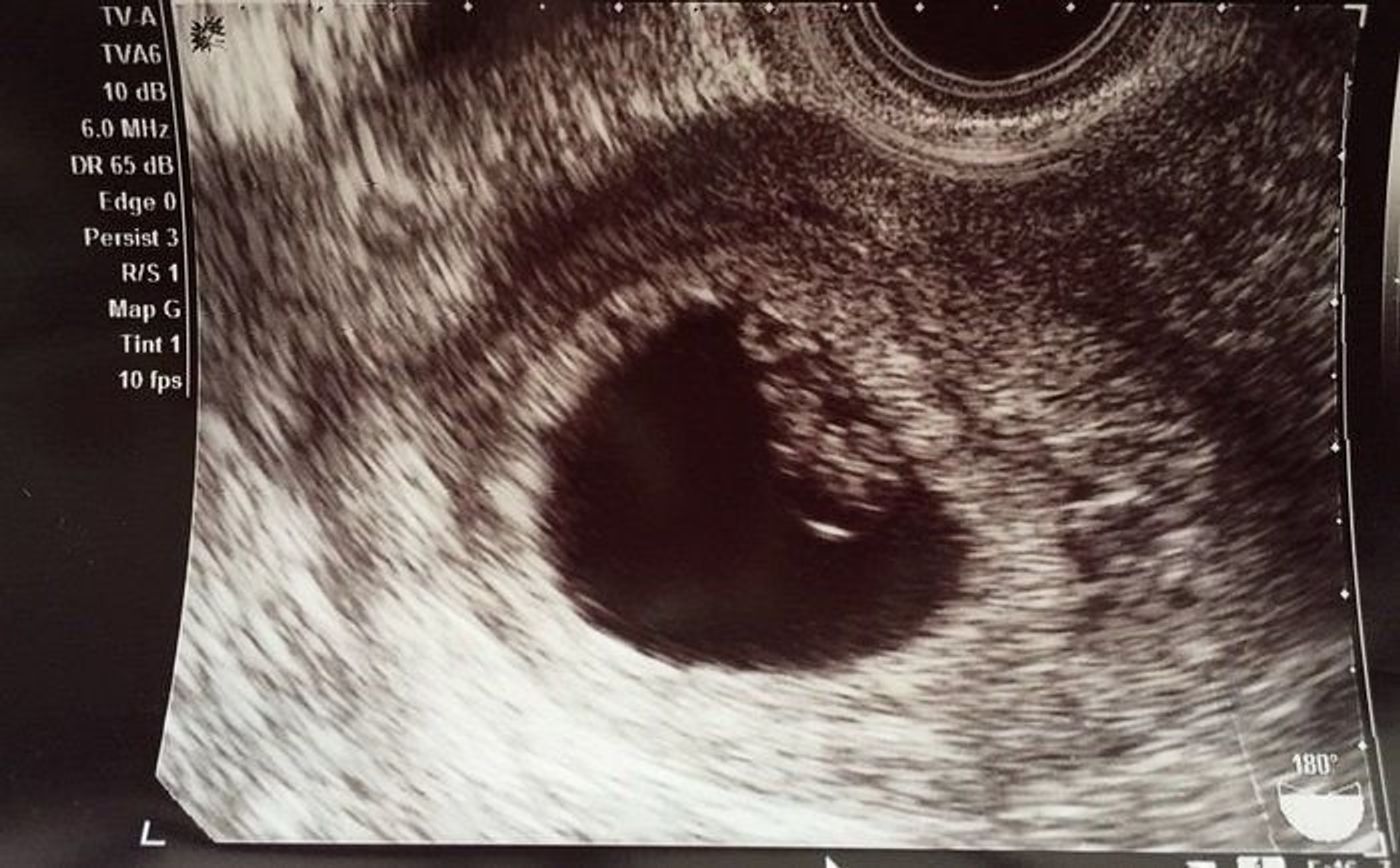

5週6日 心拍確認

5週6日 心拍確認-妊娠週 5w6d 一週間前の検診では何も見えなかったのが、今回のエコーでは197mmの大きさ。 思ったよりも大きかったです。 心拍確認の二週間後の検診が待ち遠しいです。 おなまえ かぴたん ねんれい 19 妊娠週 5w6d 薄い出血と少し生理痛のような腹痛がありました。 だけど胎嚢が1週間で13mmも成長していて驚きました! 妊娠5週6日目のエコー写真と胎嚢の大きさ ↓↓ 胎嚢(GS)は、143mm で 前回受診時(妊娠4週5日目)のときよりも大きくなっていました!!